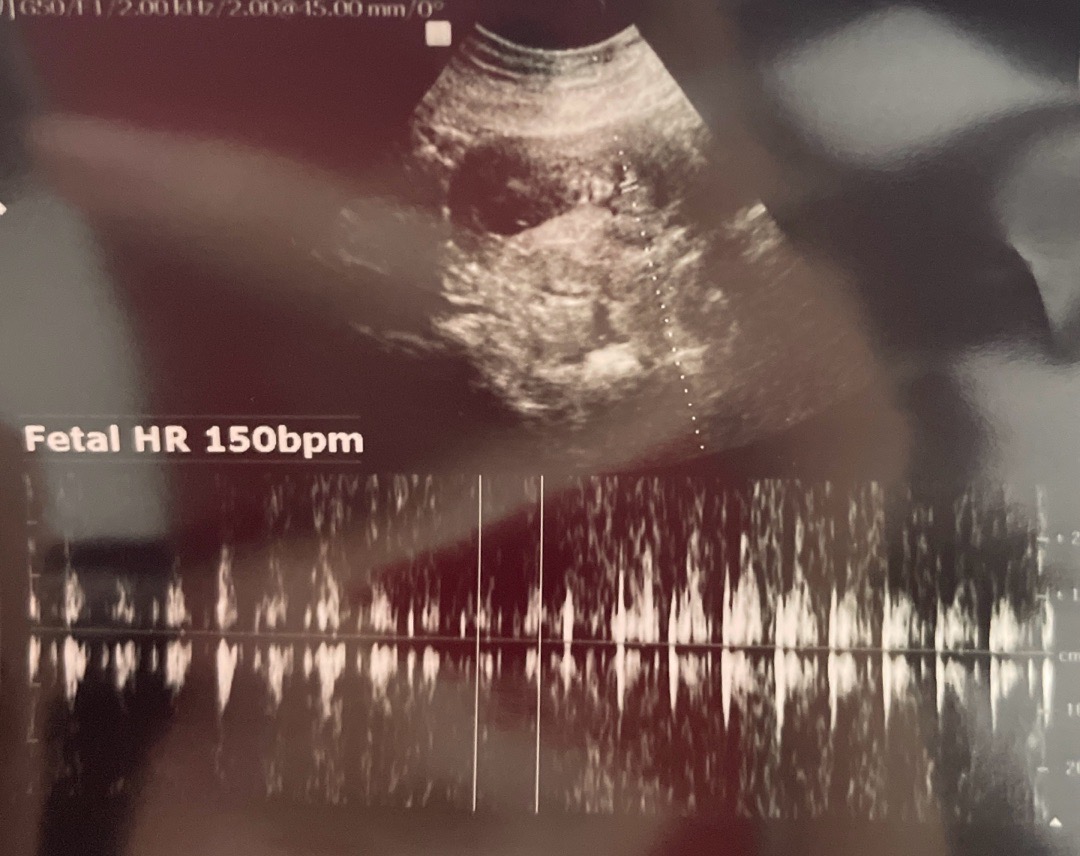

10주 3일차 심박수

아기크기는 4cm 150bpm이라구 하네요 참고로 지난 9주1일차엔 2.5cm 182bpm이였어용 ㅠ 10일만에 피비침 있어서 간건데 심박수가 훅 떨어진것같아서요 의사는 괜찮다고 정상범주라고 하는데 제가걱정되서ㅠ 주말이라 응급으로 갔더니 초음파도 뭔가 흐릿해서 뭘 찍어주신건지도 모르겟구ㅠ 마음편하려고 다녀왔다가 오히려 혼란스럽네욥 ㅠㅠㅋㅋ

10주까지 최고치찍고 그뒤로 계속 150정도 유지된다고 하더라구여 ㅎㅎ 괜찮을거에요

원래 10주차부터 점차 심박수 내려간다고 알고잇는데 아닌가요? ㅎㅎ 의사가 괜찮다고 하면 걱정 안하셔도 되실거같은데용^^~~